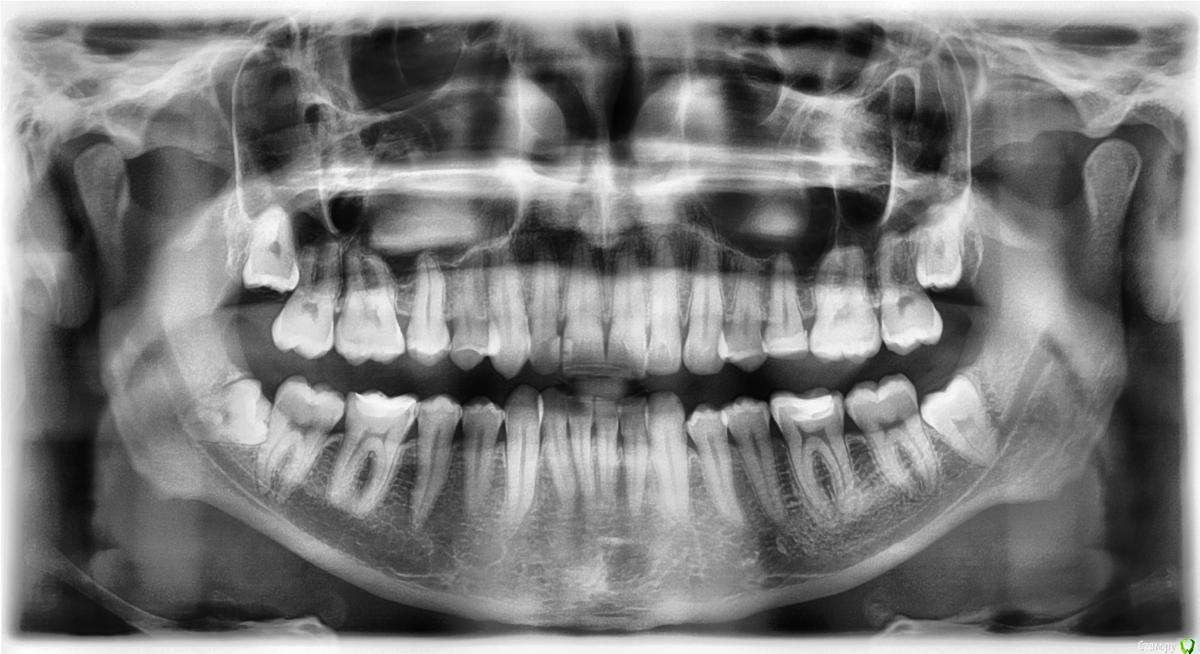

vano-box Опубликовано 10 сентября, 2016 Автор Поделиться Опубликовано 10 сентября, 2016 Доброй ночи. Мажу метрогилом, но пока как то без улучшений, уже 10 день после удаления, а ноет всё равно, разве должно так долго болеть? Сегодня сделал фото лунки, и сделал ортопанораму, скажите там всё нормально?И ещё если трогать щеку беспокоит твердая болезненная гематома, сколько она заживает в среднем? Ссылка на комментарий

red_butler Опубликовано 11 сентября, 2016 Поделиться Опубликовано 11 сентября, 2016 а ноет всё равно, разве должно так долго болеть? а как болит? На семерке похоже пульпит.за операционной областью или стоматит или оголенная кость, попробуйте попасть к другому врачу Ссылка на комментарий

vano-box Опубликовано 14 сентября, 2016 Автор Поделиться Опубликовано 14 сентября, 2016 Продолжение моей истории, был у своего доктора 12-го в понедельник, посмотрев гематому он сказал, что у меня начался процесс абсцедирования, вскрыли гематому (или это уже абсцесс не знаю) и поставили дренаж, шишка в щеке уменьшилась, стала помягче, перестала быть такой болезненной, но до конца пока не прошла, пью амоксиклав 625мг+диазолин. Собственно, что меня волнует:1. Исходя из моих снимков мог ли этот абсцесс образоваться из за инфекции в 4.6 или в 4.7 зубе? Просто ноющие боли в этих зубах продолжаются, хотя после вскрытия и установки дренажа они заметно снизились, но я почему то "втираю" себе, что все мои проблемы в одном из этих зубов. Я собственно говоря и удалил 4.8 потому, что у меня справа внизу были боли незначительные полгода(боли начались после того как мне на отколовшийся кусочек пломбы на 4,6 поставили заплатку), но два терапевта сказали мне, что виновник боли - зуб мудрости. И вот зуба нет, а проблемы остались.2 Что мне делать, что бы не началось лечение всего рта в поисках источника или подождать заживления абсцесса и ничего пока не делать? Ссылка на комментарий

red_butler Опубликовано 14 сентября, 2016 Поделиться Опубликовано 14 сентября, 2016 1. Исходя из моих снимков мог ли этот абсцесс образоваться из за инфекции в 4.6 или в 4.7 зубе? не похоже 2 Что мне делать, что бы не началось лечение всего рта в поисках источника или подождать заживления абсцесса и ничего пока не делать? когда заживет, санируйте полость рта и удаляйте остальные "восьмерки" Ссылка на комментарий